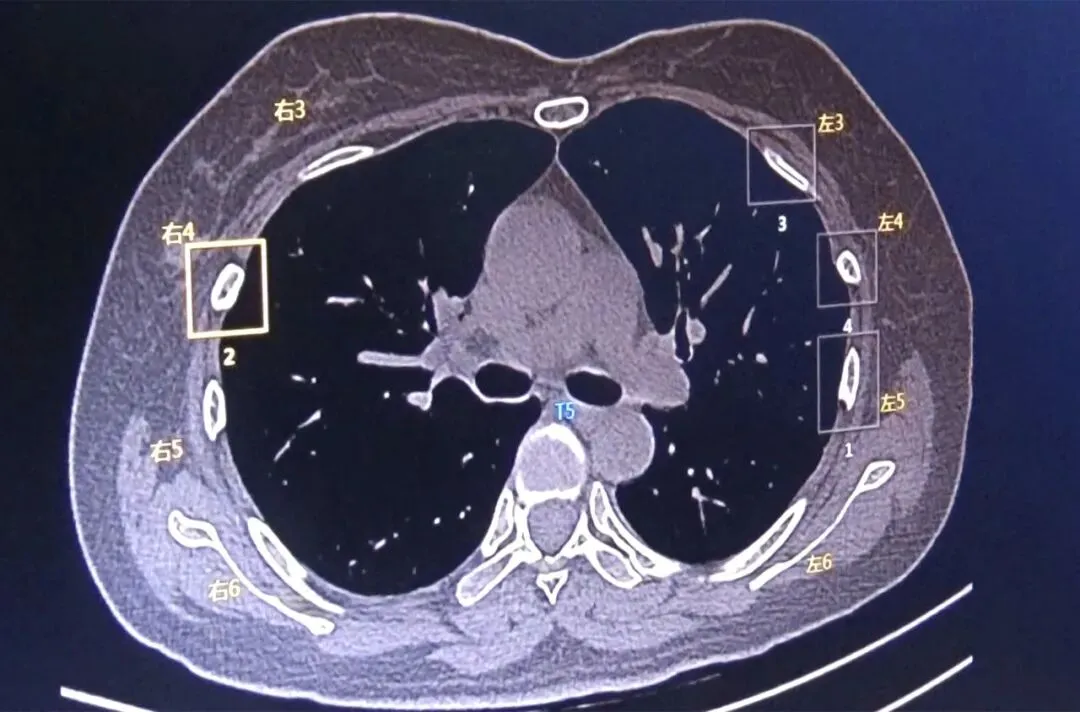

肺结节AI自动检测及量化分析:AI系统可避免肺小结节的漏诊,尤其可以大幅度降低血管旁、微小结节、淡磨玻璃结节漏诊概率,大大提高肺小结节的检出率,结合AI自动量化分析参数,有效提升肺小结节精准诊断。

肺结节AI智能随访,建立随访档案,客观准确量化肺结节随访:针对同一患者的多次影像检查,AI自动精准匹配病灶,并提供该病灶变化的多种定量参数,包括病灶大小、体积变化率、病灶类型、病灶新增或消失评估、倍增时间计算等,并且生成关于该病灶的体积变化、密度变化的趋势图,直观辅助精准随访评估,辅助肺结节治疗的预后及疗效评估。